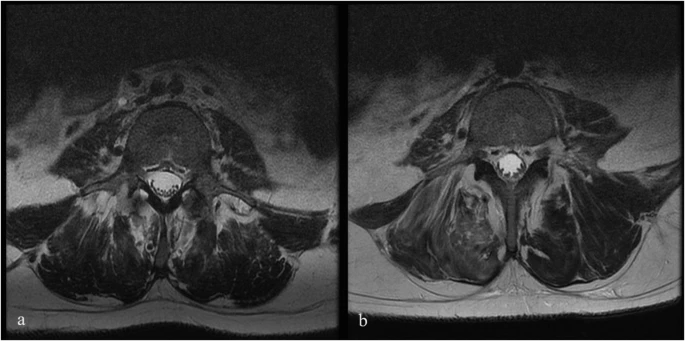

注射后血液和腦脊液檢查未發(fā)現(xiàn)異常。隨訪時(shí)MRI未見(jiàn)明顯變化;然而,在十名患者中,有八名檢測(cè)到馬尾神經(jīng)根的叢集輕度增加,有或沒(méi)有結(jié)節(jié)性增強(qiáng)的證據(jù)。在經(jīng)歷馬尾神經(jīng)根聚集或強(qiáng)化的患者中,沒(méi)有發(fā)現(xiàn)明顯的臨床相關(guān)性。圖1顯示了患者6的輸注前和隨訪MRI,該患者L4-S1水平的馬尾神經(jīng)根叢集輕度增加。表3突出顯示了所有患者干細(xì)胞注射前后的MRI變化。三名患者的SSEP有所改善。兩名患者與基線相比沒(méi)有任何變化,四名患者無(wú)法進(jìn)行解釋?zhuān)幻颊咴谡麄€(gè)研究期間具有正常的SSEP。表4突出顯示了SSEP 的發(fā)現(xiàn)和解釋。